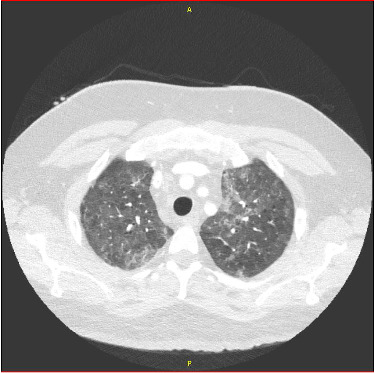

Background: The risk of cytokine release syndrome (CRS) in patients with infections prior to chimeric antigen receptor T-cell (CAR T-cell) therapy represents an important and underreported event. Patients with active infections needing prompt CAR T-cell therapy to treat aggressive hematologic malignancies remain a clinical challenge. Case Report: This case describes the clinical course of a 35-year-old male patient with relapsed/refractory T-cell/histiocyte-rich large B-cell lymphoma who received axicabtagene ciloleucel. The patient developed ASTCT Grade II CRS on day +5, necessitating hospital admission and intravenous antibiotics, dexamethasone and tocilizumab. The patient was found to have a Pneumocystis jirovecii pneumonia (PJP) infection 3 days prior to CAR T-cell infusion and cytomegalovirus (CMV) viremia 3 days after CAR T-cell infusion. He received TMP-SMX for 21 days to treat PJP and valganciclovir to treat CMV viremia. PET/CT on day +26 demonstrated near resolution of pulmonary nodules and significant partial response of disease according to Deauville criteria. Conclusion: This case highlights the risk of CRS in immunocompromised patients with infections, and presents a unique case of CRS associated with PJP and CMV infections. Although the patient's clinical course was fraught with complications, he achieved a significant partial response to CAR T-cell therapy with the help of a multidisciplinary medical team.